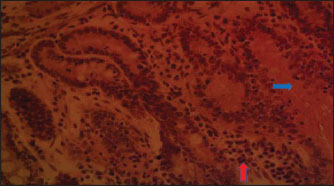

The histology of the duodenum in rabbits fed with diet 2 (TDLM) is presented in Fig. 2. The slide reveals that the duodenum in rabbits consuming Tithonia diversifolia shows moderate necrosis of the crypts of Lieberkühn and mucosal epithelial cells. The histology of the duodenum in rabbits fed with diet 3 (PBLM) is depicted in Figure 3. The histological slide indicates that the duodenum of rabbits fed with Parkia biglobosa exhibits moderate necrosis of the Lieberkühn crypt and mucosal epithelial cells, accompanied by infiltration of inflammatory cells.

Fig. 2. (TDLM): Section of the intestine showing moderated necrosis of Crept of Lieberkühn (arrow) and mucosal (arrow head) epithelial cells (x400; H & E).

Fig. 3. (PBLM): Section of the intestine showing moderated necrosis of Crept of Lieberkühn (blue arrow) and mucosal (arrow head) epithelial cells, with infiltration of inflammatory cells (red arrow) (x400; H & E).

In the NLM shown in Figure 1, the mucosal lining was complete, with the Lieberkühn villi and crypts properly arranged. The epithelial layer, largely composed of absorptive enterocytes and goblet cells, was well preserved and did not show cellular erosion or necrosis (An et al., 2022). The lamina propria appeared to be free of inflammatory infiltrations, and the make-up was not atrophied or distorted, indicating a healthy mucosal barrier and optimum operational capacity (France and Turner, 2017). The TDLM (Fig. 2) had effects that showed cellular disintegration of the Lieberkühn crypts, signifying epithelial rejuvenation (Liu et al., 2019). At the same time, mucosal epithelial inner layer necrosis, shown by disturbed cellular structure and cytoplasmic degradation, suggests a distorted mucosal barrier that may amplify absorptivity, poor nutrient assimilation, and increased susceptibility to enteric pathogens (Chistiakov et al., 2014; De Medina et al., 2014). These observed changes can be due to the secondary metabolites like saponins, alkaloids, phenolics, and tannins present in Tithonia diversifolia, which are known to cause cytotoxic, anti-proliferative, and membrane-disrupting activities in the GIT tract when taken unprocessed (Abdelsalam and Fathi, 2023). These observations demonstrate the need for detoxification, quantification, and probably fermentation when incorporating TDLM into the diet of local rabbits (Abd-Elghany et al., 2021). Although TDLM provides a good source of nutritious and phytogenic benefits, its raw inclusion must be controlled to avoid compromising gut integrity and performance (Sugiharto et al, no date). In the observed PBLM in Figure 3, the necrosis in the crypt of Lieberkühn shows disturbance of the proliferative region crucial for epithelial regeneration and intestinal homeostasis (Chistiakov et al., 2014). Impairment of the crypts affects enterocyte production, which may cause weakened absorptive and digestive effectiveness in the small intestine (Buckley and Turner, 2018). Concurrently, mucosal epithelial cell degeneration and necrosis show intestinal barrier failure, increasing the danger of luminal antigen translocation and mucosal susceptibility (An et al., 2022). The permeation of inflammatory cells, mainly lymphocytes and macrophages, demonstrates a limited immune response that may be a reaction to epithelial injury caused by phytochemicals in Parkia biglobosa leaves (Franz et al., 2019). These bioactive constituents possess antioxidant and antimicrobial properties and may cause cytotoxic effects at high levels of inclusion in unprocessed form. Tannins and saponins can tamper with membrane integrity, modify gut microflora, and trigger mucosal irritation (De Medina et al., 2014). These effects are consistent with the inflammatory and degenerative changes observed in the duodenal mucosa (Chistiakov et al., 2014; De Medina et al., 2014). The observed necrosis in the crypt that controls epithelial cell production and mucosal renewal in rabbits fed SNLM indicates weakened cellular turnover (Buckley and Turner, 2018). Moreover, the loss of mucosal epithelial cells’ integrity shows that the absorptive and protective barrier is compromised, which is crucial for nutrient uptake and host protection (Liu et al., 2022). The infiltration of inflammatory cells, principally comprising lymphocytes and plasma cells, into the lamina propria, as shown in Figure 4, demonstrates an ongoing immune response that may have been prompted by mucosal or antigenic disturbance from biologically active compounds in Synedrella nodiflora. If the concentration is not regulated, this can lead to a cytotoxic or pro-inflammatory effect on the mucosa of the GIT (Jha et al., 2019). Specifically, saponins are known to disrupt membranes and increase gut penetrability, possibly leading to reactionary inflammation and epithelial damage (Ohimain et al., 2020). Necrosis of the Lieberkühn crypt observed in the LMM (Fig. 5) and damage to the mucosal epithelial cells affect the intestinal epithelium, compromising absorptive and secretory activities crucial for gut health (Buckley and Turner, 2018). This pattern is consistent with that observed in other leaf meals; however, the infiltration of inflammatory cells appeared mild, suggesting a moderate but continuous controlled immune response, possibly to clear away cellular fragments and restore mucosal integrity (Chistiakov et al., 2014; De Medina et al., 2014). This trend aligns with subacute intestinal damage, where soreness is present but not distressing, enabling mucosal recovery if the injurious stimuli are removed (France and Turner, 2017; An et al., 2022).